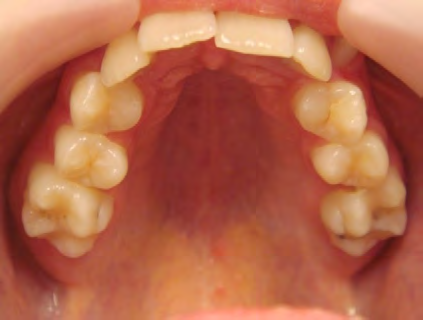

All of the patients below had been told they required extractions by orthodontists, some insisting that they could not be treated without extractions.

They were all treated without extractions, head gear or facemasks at Vakresmil and represent just a small sample of cases treated between 2004–2014.

The patient below had severe crowding of both upper canines and the lower right 5. The upper 4’s and 2’s were actually in contact.

Below are cases treated at Vakresmil without extractions within the last three years. The families had been told, “It is simply not possible for your child to be treated without extractions” by orthodontists. Judge for yourself if that was right or wrong.